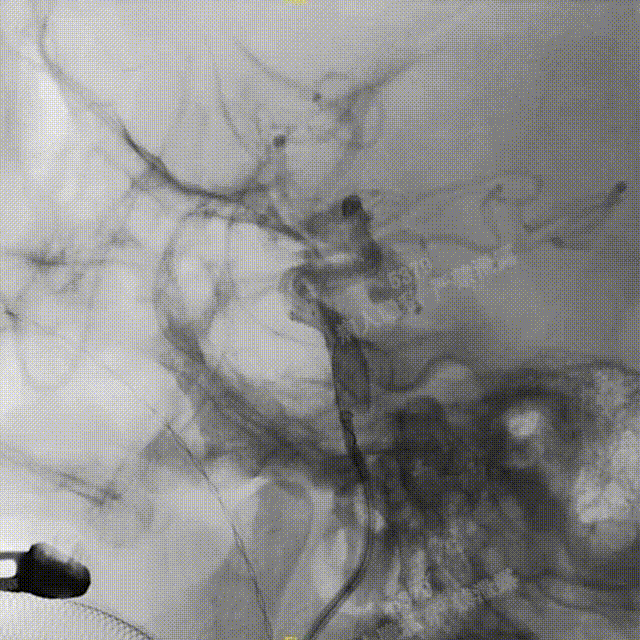

造影确认,载瘤动脉通畅、支架远端分支血流通畅、支架贴壁良好、动脉瘤内造影剂滞留。

撤出支架系统,无需后处理按摩。

正、侧位造影及术后CT复查结果观察,载瘤动脉通畅、支架贴壁良好、动脉瘤内造影剂滞留、颅内未见明显异常。